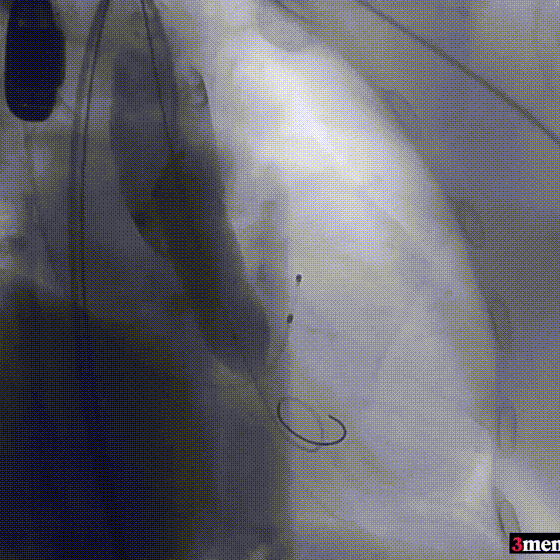

手术过程回顾:

患者全麻后,右侧股动脉建立主入路,主动脉根部造影显示主动脉瓣明显钙化。心室内轻微反流,主动脉及心脏情况整体较为稳定。直头导丝跨瓣后,在超硬导丝支撑下,瓣膜输送系统顺利跨瓣。在180次/分快速心室起搏下,确定降压至50mmHg后选择18mm球囊进行预扩张。在球囊扩张后,该患者血压未见升高,随即进行胸外按压,同时根据术前评估及球囊预扩情况,选取直径23mm瓣膜果断快速进行瓣膜定位并释放。瓣膜释放后患者心律和血压趋于平稳。

主动脉根部造影

直头导丝跨瓣

球囊预扩

瓣膜定位并行胸外按压